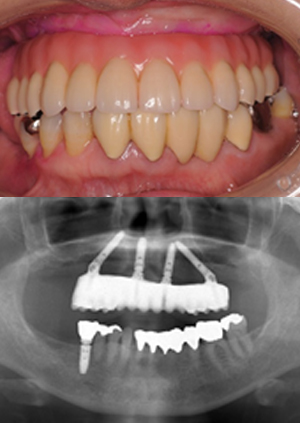

オールオン4症例②

1. all on 4②治療前

2. all on 4②治療後

主訴 上下の入れ歯が合わない

歯が揺れて噛めない

治療内容 受け口で義歯合いづらく歯周病が進行しているため残っていた歯を全身麻酔下にて全てを抜歯して同時に上下8本のインプラントを埋入翌日に固定式の仮歯を装着した。 骨とインプラントが結合するのを待ち、最終日な上部構造を装着した。

治療期間 10か月

治療金額

• 全身麻酔および1泊入院費用:

¥275,000(税込)

• ALL on 4 手術費用:

¥1,210,000×2(税込)

• 上部構造(チタンハイブリッドタイプ、噛む面はメタル)